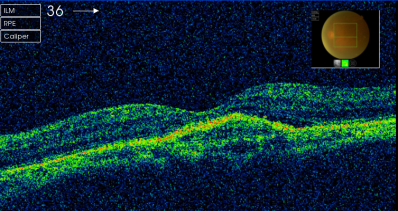

患者曹某,80岁,因双眼视力下降1年就诊。检查右眼视力0.3,左眼0.08,裂隙灯检查双眼晶体皮质混浊明显,散瞳后眼底检查见右眼黄斑区金箔样反光,左眼黄斑区中心凹反光消失。患者眼底荧光照影检查显示左眼黄斑区有血管荧光的渗漏,眼科光学相干断层扫描(OCT)检查显示右眼有黄斑前膜增生,左眼脉络膜新生血管膜(图片1)。诊断:左眼老年性黄斑变性(脉络膜新生血管),右眼黄斑前膜,双眼老年性白内障。患者于2013年3月行眼内注药(雷珠单抗)。3月后复诊左眼视力0.1,复查OCT示左眼视网膜新生血管膜消退(图片2),建议先行左眼白内障手术治疗。

图片1左眼:脉络膜新生血管膜